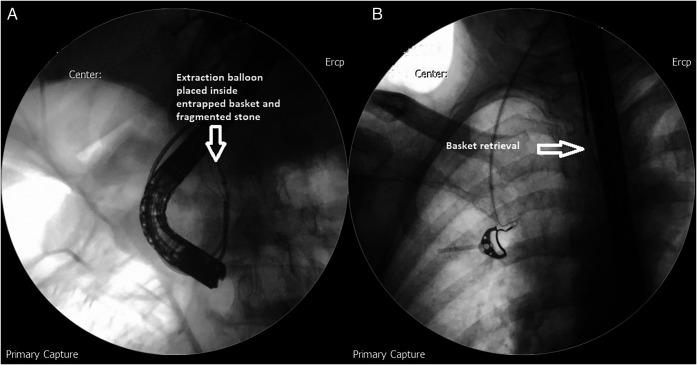

Cholangioscope-Guided Electrohydraulic Lithotripsy as a Rescue Technique for an Impacted Dormia Basket With Large Common Bile Duct Stone.

Impaction of Dormia basket while extracting common bile duct (CBD) stones during endoscopic retrograde cholangiopancreatography is a well-known but relatively rare complication. Its management could be very challenging and may require percutaneous, endoscopic, or major surgical intervention. In this study, we present a case of a 65-year-old man with a history of obstructive jaundice secondary to a large CBD stone. For stone extraction, mechanical lithotripsy with a Dormia basket was attempted resulting in its entrapment within CBD. Subsequently, the entrapped basket and large stone were retrieved using a novel technique of cholangioscope-guided electrohydraulic lithotripsy with excellent clinical outcomes.

在内镜逆行胰胆管造影术期间,使用多尔米亚取石篮取出胆总管结石时发生嵌顿是一种广为人知但相对罕见的并发症。其处理可能极具挑战性,可能需要经皮、内镜或大型手术干预。在本研究中,我们报告了一例65岁男性患者,其有因胆总管大结石继发梗阻性黄疸的病史。为取出结石,尝试使用多尔米亚取石篮进行机械碎石,结果取石篮被困在胆总管内。随后,采用一种新型的胆管镜引导下的电液压碎石技术取出被困的取石篮和大结石,临床效果极佳。